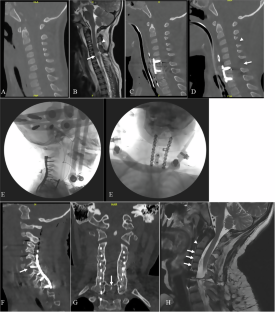

We identified 5 patients with the mean age of 4.4 years (range 2–6 years) who all had spinal cord injury with subluxation or dislocation at C6–7. All patients underwent posterior cervico-thoracic fixation with mandibular instrumentation from C2 to the upper thoracic spine. There was one complication of a right vertebral artery occlusion by screw placement, which did not cause harm. Suboptimal screw placement was detected in 18.4% of screws, but no revision was needed, since it was asymptomatic. All patients fused successfully without significant hardware failure. The mean time of follow up was 91 months ranging from 33–187 months.

Mandibular screw and plate fixation was effective to treat the acutely traumatic unstable subaxial cervical spine in the young pediatric population. The rate of suboptimal screw placement may be reduced by placing shorter screws into the lamina, pedicles, or facets if the plate hole does not align for a standard trajectory needed for lateral mass or pedicle screw placement.